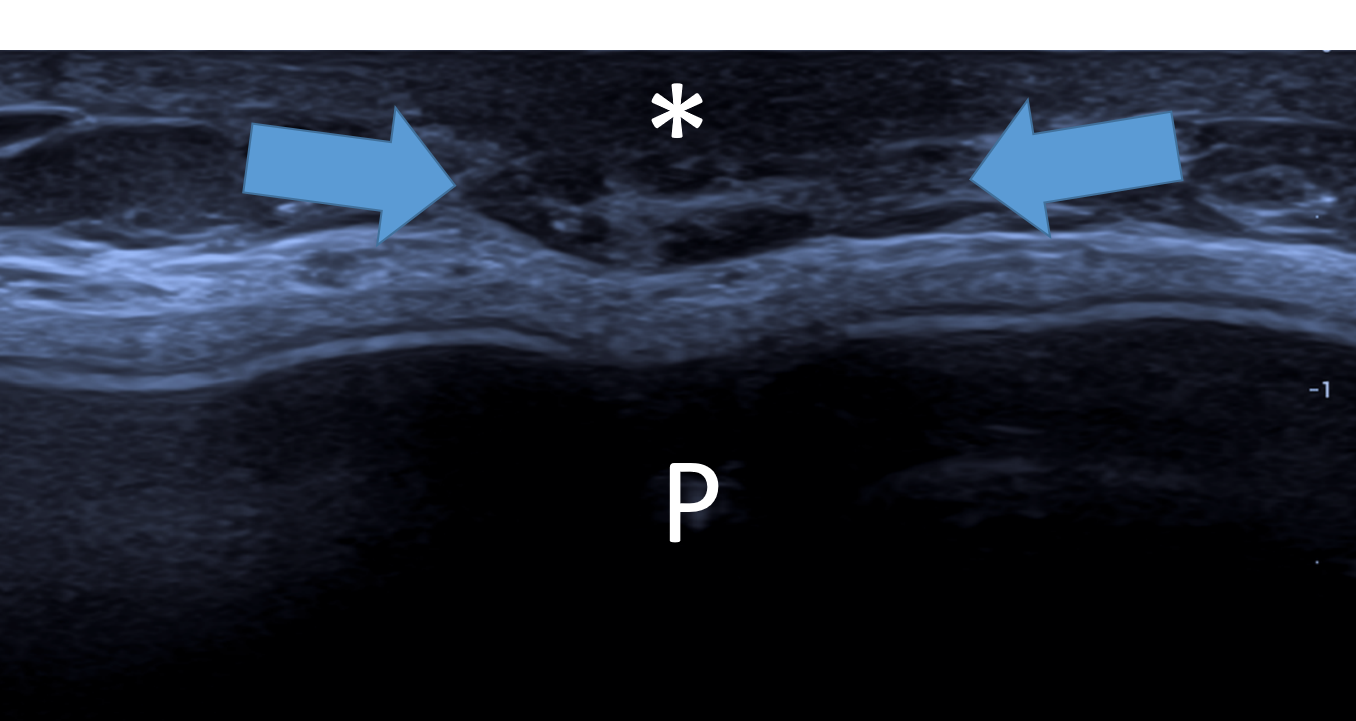

Da superfície para a profundidade, identificam-se: a pele ecogênica; a gordura subcutânea ou pré-glandular, geralmente isoecóica e atravessada pelos ligamentos de Cooper; a zona fibroglandular, de ecogenicidade predominantemente aumentada; e a gordura retroglandular, novamente isoecóica. Todo esse conjunto repousa sobre o músculo peitoral maior, cuja ecogenicidade é semelhante à da gordura. Além das próprias camadas, as interfaces entre elas — como as fáscias pré- e pós-glandulares — constituem marcos anatômicos importantes para a localização das lesões mamárias. O reconhecimento sistemático dessas camadas e de seus limites é essencial para a correta interpretação dos achados ultrassonográficos e para uma comunicação mais precisa da localização das lesões.

A maior parte dos ductos e das unidades funcionais da mama, incluindo as unidades ducto-lobulares terminais (TDLUs), localiza-se na zona glandular, também denominada zona mamária. Essa região é delimitada anteriormente pela fáscia pré-glandular e posteriormente pela fáscia pós-glandular, que definem seus limites anatômicos à ultrassonografia.

A fáscia pré-mamária atua como uma barreira anatômica relativa à progressão superficial das lesões originadas na zona glandular. Como consequência, muitas lesões tendem a crescer preferencialmente no sentido ântero-posterior, ultrapassando planos teciduais, em vez de se expandirem paralelamente à pele. Esse comportamento anatômico explica, em parte, o padrão “taller-than-wide”, considerado um critério morfológico suspeito na ultrassonografia mamária.